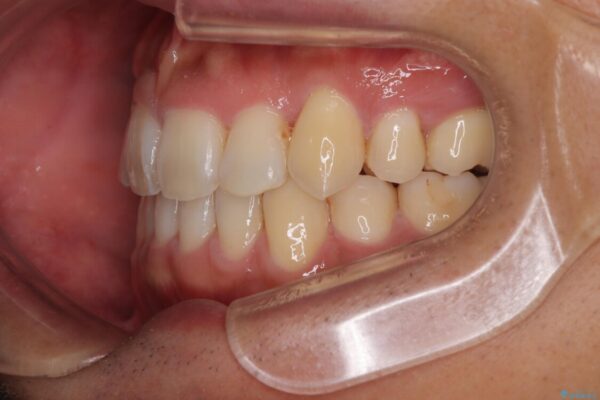

「八重歯を治したい」とご相談いただいた患者様の症例をご紹介します。

上下の前歯部に強い叢生(ガタガタの歯並び)があり、そのまま歯を並べると出っ歯になってしまう可能性がありました。

治療前

• 八重歯と前歯のガタガタを抜歯矯正で治療|クリアブラケット使用例 治療前画像